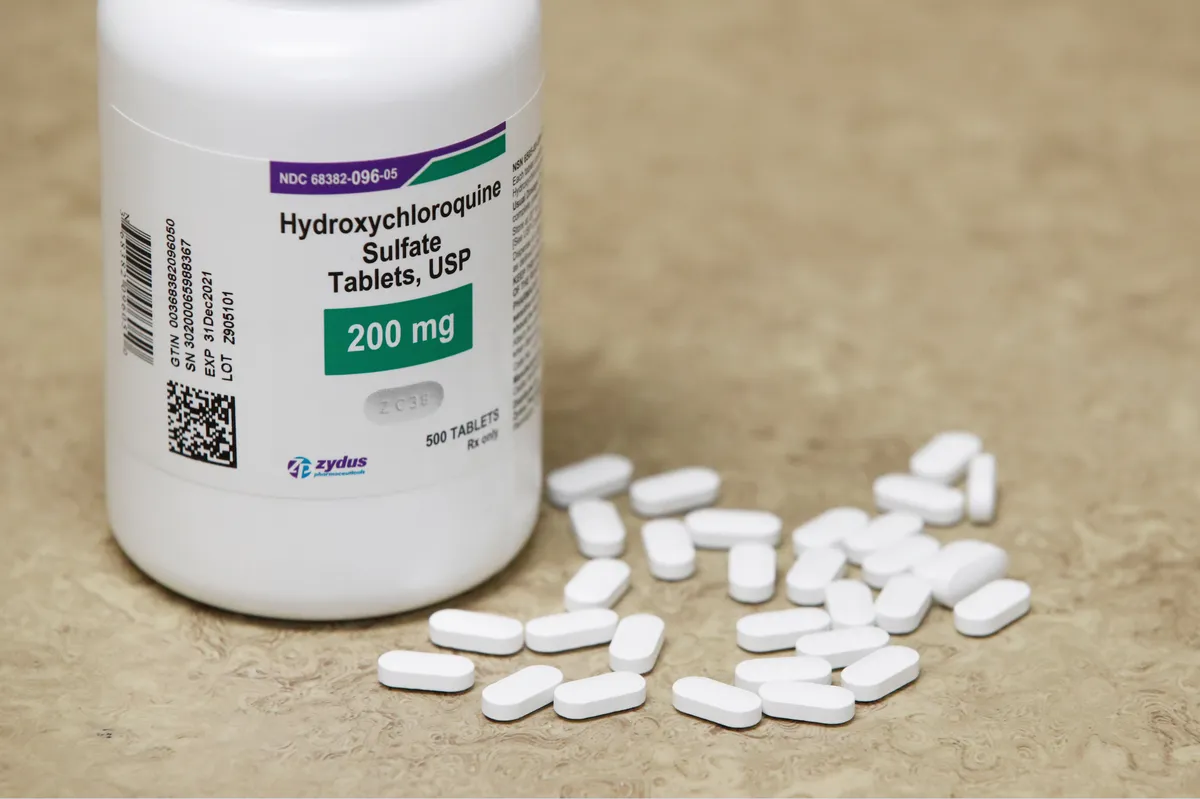

Prurido na DRC: passo a passo prático que funciona

Prurido na DRC: passo a passo prático que funciona

Será que o tratamento de Prurido na Hemodiálise deve se concentrar apenas no controle do Fósforo? Confere dicas simples e práticas de como seguir o tratamento